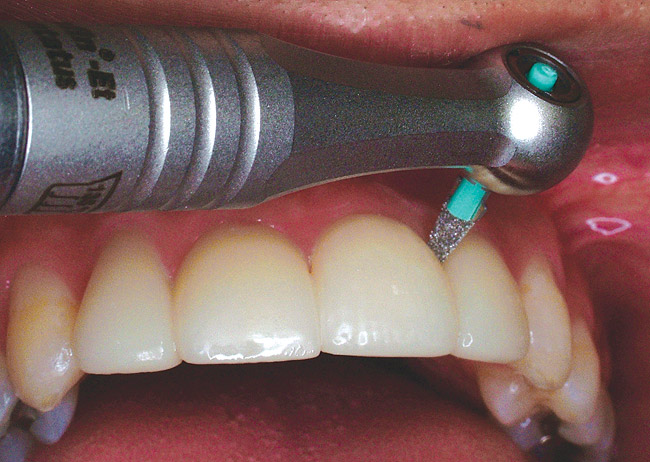

Larger anterior restorations, such as Class 4, incisal edge repairs, and complete composite resin facial veneers, typically involve more gross shaping with finishing burs and submicron finishing diamonds on a high-speed handpiece, followed by additional finishing with abrasive discs and/or rubber points. To establish esthetic form to curved surfaces on long restorations that cover the full length of the tooth, use narrow, long finishing burs (Figure 1) or diamonds with safe-tipped ends (Figure 2).While finishing burs and diamonds can be used either wet or dry, the authors prefer using them dry and suctioning the composite dust throughout the procedure. The authors have found that by working with a dry field and a light touch, they can better visualize the shape and contour of the composite resin surface. Longer restorations also can be finished by judiciously using small sections of coarse and medium grit finishing discs. Most available discs have small metal hubs to avoid marring the composite surface by accidentally hitting the composite with the metal hubs of the disc (Figure 3). Some manufacturers have placed their discs on silicone sheaths that slip over the metal mandrel, totally eliminating the potential for marring the composite resin surface (Chipless Wheel, Shofu Dental Corp, San Marcos, CA; EP® Composite Polishing System, Brasseler USA, Savannah, GA).

Figure 1  Long, thin, 12-bladed composite resin finishing bur (SS White Burs, Inc, Lakewood, NJ) trimming the facial surface of a composite veneer.

Figure 1

Figure 2  Fine finishing diamond marginating a gingival margin (SS White Burs, Inc).

Figure 2